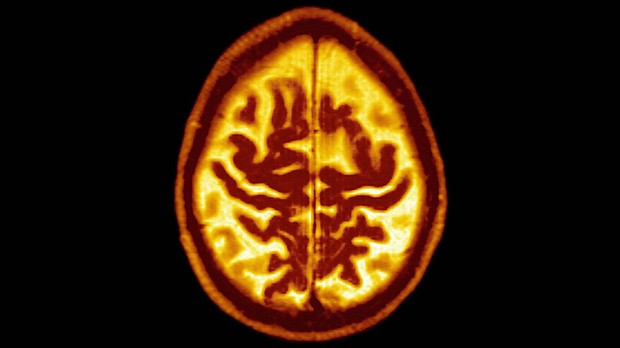

Late Onset Alzheimer's Disease Senile Dementia. Symmetric Enlargement Of Cerebral Sulci Suggests That Cortical Gray Matter Is Affected.

Lowering blood pressure could cut risk factor for dementia

Intensive lowering of blood pressure, to a less than 120 mm Hg level, can have a measurable impact on mild cognitive impairment (MCI) -- a well-established precursor of dementia, a new study finds.